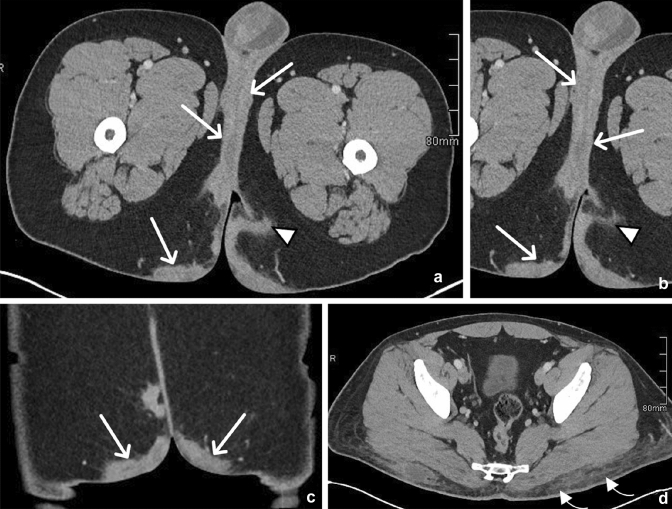

Fig. 1.

43-year-old male with bilateral pectineal muscle myonecrosis. Axial (a) and coronal (b) CT images of the abdomen and pelvis demonstrate ill-defined muscle enlargement and decreased attenuation of bilateral anteromedial compartments of the upper thighs (arrows). Axial (c) and coronal (d) T1W fat-saturated post-contrast MR images demonstrate bilateral peripheral enhancement (arrowheads) of the pectineus muscles surrounding central non-enhancing (arrows) muscle fibers representing myonecrosis